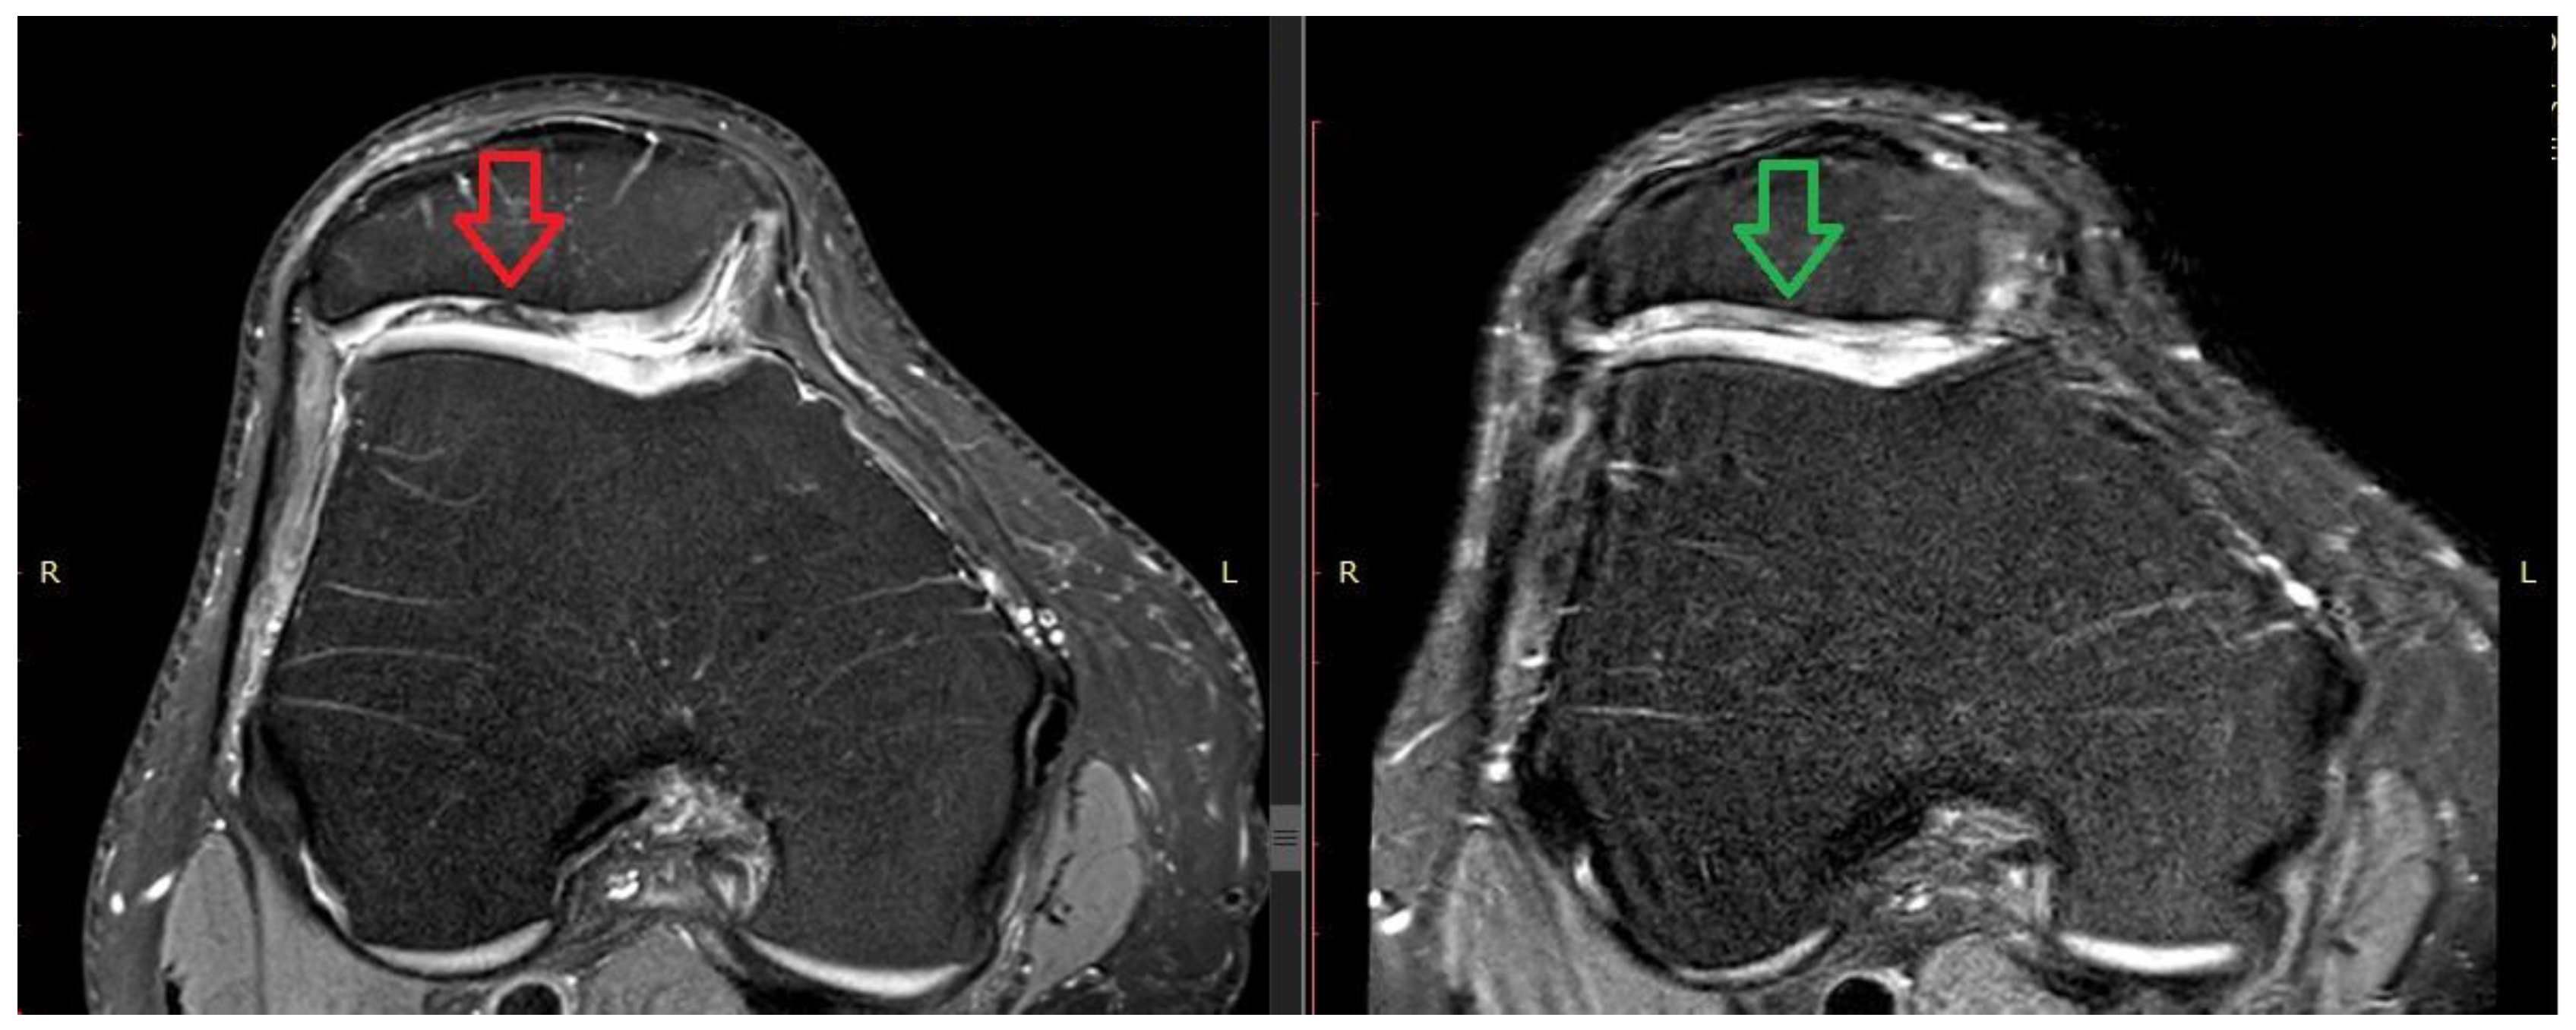

The analysis showed that the groups did not differ from each other in the measurements and the final score in the BMAC-MSCs group was similar to that in the hUCB-MSCs group with no statistically significant differences. Example magnetic resonance images from the BMAC-MSCs group are shown below (Figure 4).

Figure 4. The pre-operation (on the left) versus 12 months post-operation (on the right) MRI images. The patient from the BMAC-MSCs group shows a local chondral lesion (indicated by the red arrow) on the patella. The green arrow highlights the observed effect of the therapy after one year.